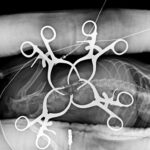

頻繁に嘔吐・下痢をするワンちゃんの精密検査依頼で内視鏡検査のご紹介がありました。内視鏡検査で上部・下部消化管を検査し、粘膜を採取し病理組織検査に出しました。結果は「胃:らせん菌感染を伴う慢性胃炎(中程度)/結腸:慢性腸炎(軽度)」とのことでした。その後かかりつけの先生のところ […]